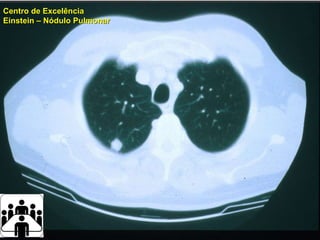

Paciente Centro de Excelência Einstein  –  Nódulo Pulmonar

Paciente Centro deExcelência Einstein – Nódulo Pulmonar